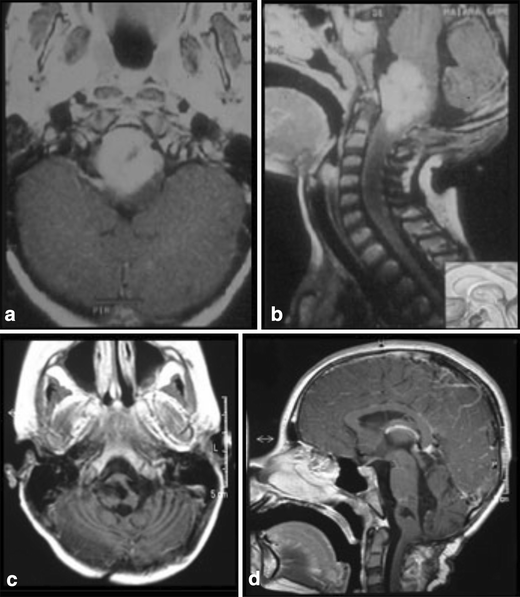

a, b 8-month-old patient with a large lesion in the anterior and superior portion of the pons, approached via orbito-fronto zygomatic via the supratrigeminal entry zone. c, d 6-month postoperative follow-up after complete resection of the lesion

a, b 10-year-old patient with tetraparesis. Tumor operated with a pre-sigmoid approach. c, d Postoperative control 10-year after gross total resection, showing no evidence of tumor

figure 17

a, b Superior and posterior pontine tumor approached via suboccipital telovelar approach with the point of entry into the pons through the suprafacial triangle. Astrocytoma grade II. c, d Postoperative control showing gross total resection

figure 18

a, b 5-year-old patient with pontine lesion approached by infrafacial entry point. c, d 8-year follow-up. Pilocytic astrocytoma